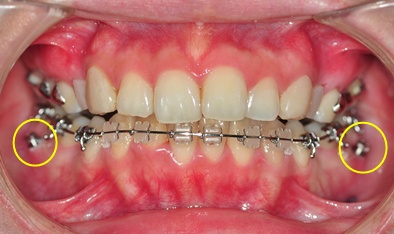

하악 스크류 심은 사진 보여드릴께요~ ^^

└▷ 짜잔~ 이렇게 어금니 아래 안쪽에 심었습니다~ + _+

( 친절하고 예쁜 치위생사선생님이 이렇게 잘 보이게 찍어 주셨어요~ ^^